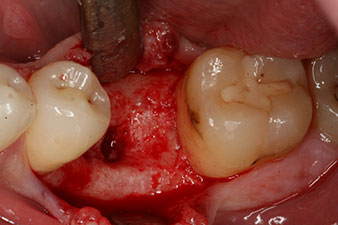

peri-implant bone deficit

Fig. 5: The peri-implant bone deficit must be compensated with autogenous bone chips to restore the peri-implant tissue contour.

These values could have indicated open healing or even immediate restoration. Due to the insufficient crestal bone volume at the implant, the region was augmented with the bone chips collected during preparation of the implant bed and sutured to exclude saliva.